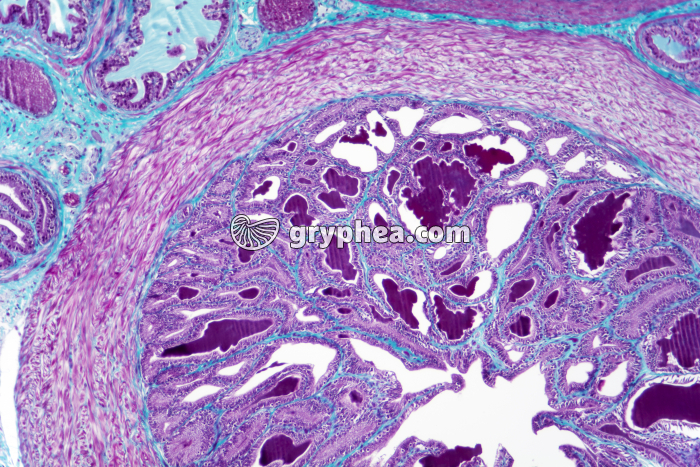

Vésicule séminale CT x25

Les vésicules séminales sont des organes pairs dont les sécrétions sont déversées dans les canaux éjaculateurs qui se rejoignent et confluent avec l’urêtre au niveau de la prostate. Leur structure alvéolaire présente des replis anastomosés se rejoignant au centre de la lumière des cavités et suggère une sorte de dentelle. Comme pour la prostate, les vésicules séminales possèdent une adventice externe, une musculeuse (muscles lisses longitudinaux externes et muscles circulaires internes) peu épaisse. et une muqueuse dont l’épithélium comporte des cellules cylindriques. Les sécrétions des vésicules séminales, riches en fructose, représentent environ 70 % du liquide spermatique.